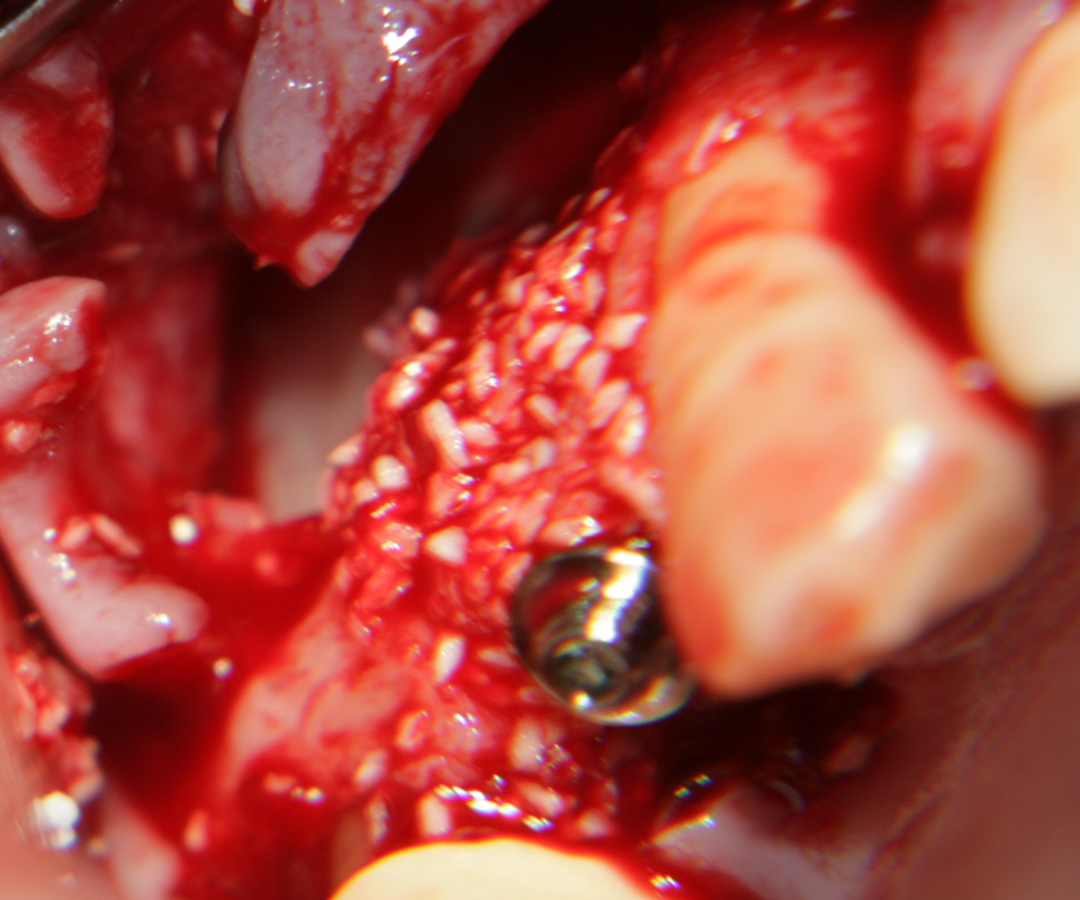

При операции с цел изграждане на допълнителн костна тъкан (костна пластика) винаги е добре да се перфорира кортикалната пластинка на костта. През тези перфорации излизат костни клетки, които постепенно прорастват в котозаместващия материал и синтезират нова костна тъкан. Перфорациите могат да се извършат с кръгло борче или с АСМ - фрезата на Neobiotech - Южна Корея.

С фрезата за автогенна кост се извършва много бързо и лесно отнемане на

кортикалната кост

Автогенна кост

Около винтовете се поставя костозаместител, добре е да се размеси с

автогенна кост